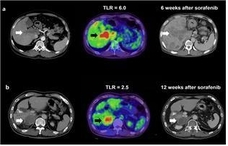

진행성 간암, PET/CT 검사로 치료 결과 예측 가능

- 2017-12-12 18:32

- 김경애 기자